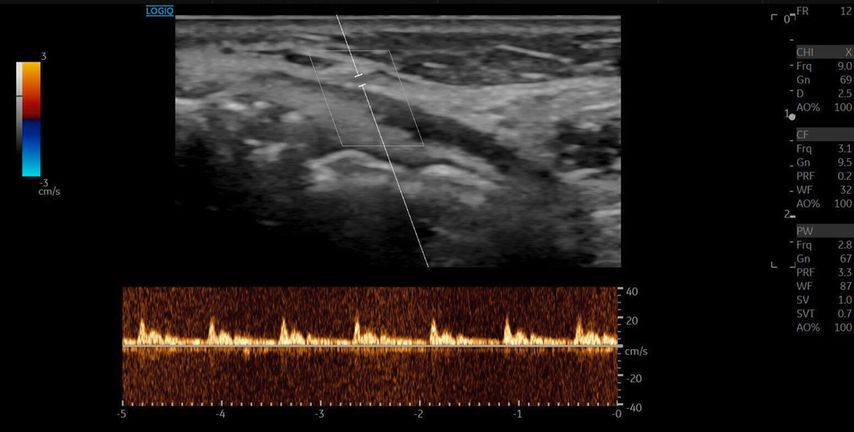

Die A. facialis imponierte beim Austritt im Bereich des Musculus masseter (oberhalb der Kieferlinie) vasospastisch mit einem maximalen Durchmesser von 1mm. Die abgeleitete systolische Spitzengeschwindigkeit betrug trotz der bestehenden Ischämie 20cm/s, ohne enddiastolische Komponente, was auf eine weitere periphere Vasokonstriktion hindeutete (Abb. 2 und 3).

Die A. facialis ist die Hauptarterie zur Blutversorgung des Gesichts und entspringt aus der A. carotis externa. Sie hat einen stark geschlängelten Verlauf und bildet zahlreiche Anastomosen mit benachbarten Arterien. Ihr Durchmesser variiert entlang ihres Verlaufs: Am Unterkieferrand liegt der mittlere Durchmesser bei 2,4mm, in der Wangenregion bei 1,9mm und im Bereich der Nasolabialfalte bei etwa 1,5mm. Die A. angularis, der Endast der A. facialis, weist einen Durchmesser von ca. 1,2mm auf. Die Flussgeschwindigkeit variiert je nach Region, beträgt aber durchschnittlich zwischen 20–50cm/s.1

Sonografisch lässt sich die A. facialis am besten an der Vorderseite des Musculus masseter detektieren. Sie zeigt eine deutliche Pulsation, und ihre Hauptäste – A. labialis inferior, A. labialis superior und A. angularis – sind aufgrund ihrer oberflächlichen Lage gut darstellbar.